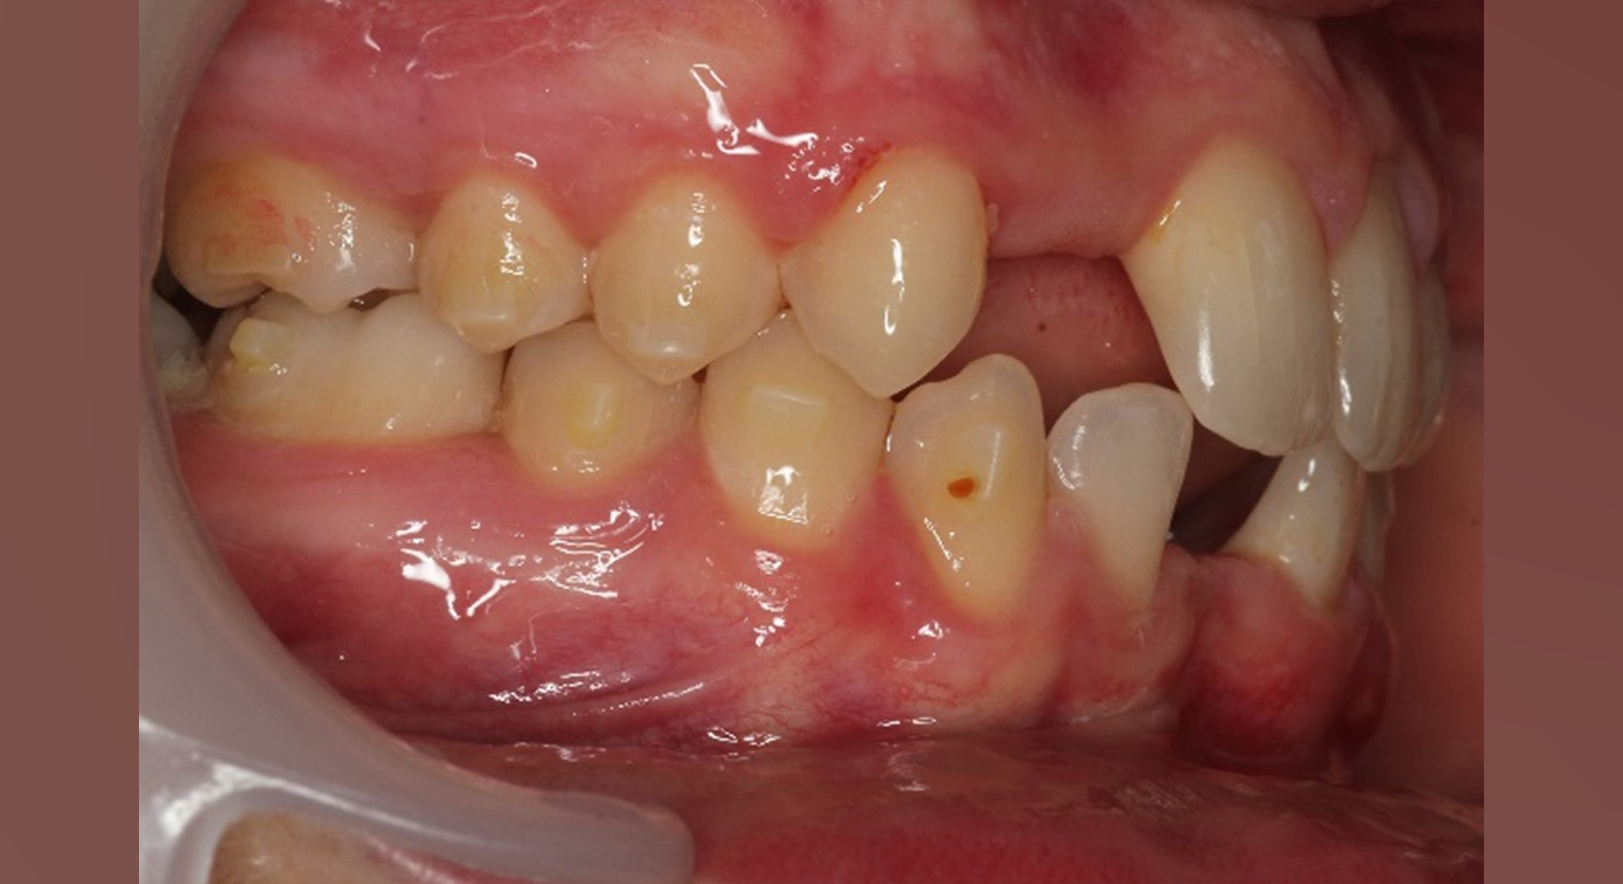

Skeletal Class II due to mandibular retrognathia, proclination of maxillary incisors, narrow arch creating a V-shaped arch, agenesis of 12, 31, 41, hyperdivergent facial pattern, moderate deep bite (2 mm), increased overjet (9 mm), asymmetric canine and molar Class II due to mandibular deviation to the left, maxillary midline deviation related to agenesis of 12, distal rotation of 35 and 45, and pronounced lower curve of Spee.

Lower arch: 31 active aligners

Incisor intrusion using frog staging

Vertical attachments on lower incisors for improved tipping control

Space opening for 31 and 41

Elastics protocol

Class II elastics: 4.5 oz, 14 hours/day

Hooks on 13 and 23, button cut-outs on lower molars